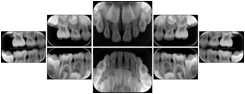

OO.1.3 Cardiology

Cardiac stress testing acquires images in at least two patient states, rest and stress, and typically with several different views of the heart to highlight function of different cardiac anatomic regions. Image review typically involves simultaneous display of the same anatomy at two patient states, or multiple anatomic views at one patient state, or even simultaneous display of multiple anatomic views at multiple states. This applies to all cardiac imaging modalities, including ultrasound, nuclear, and MR. The American College of Cardiology and American Society of Nuclear Medicine have adopted standard display layouts for nuclear cardiology rest-stress studies.

Stress Echocardiography Structured Display

Figure OO-5. Stress Echocardiography Structured Display

Stress-Rest Nuclear Cardiography Structured Display

Figure OO-6. Stress-Rest Nuclear Cardiography Structured Display